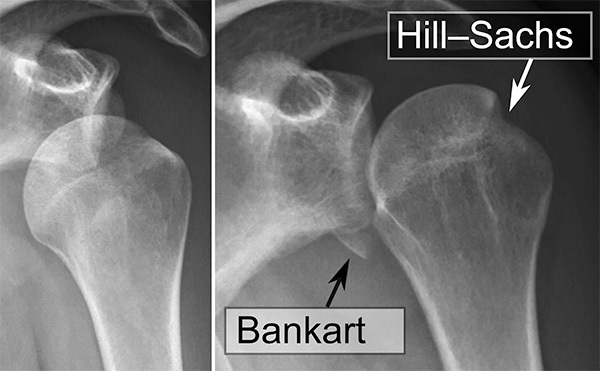

Shoulder dislocations account for up to half of all major joint dislocations.42 The shoulder can dislocate in multiple directions because of the joint’s natural instability, with anterior dislocation being the most common. Patients with previous shoulder dislocations are more prone to repeat dislocation.42,43 Injury to the axillary nerve during shoulder dislocation is as high as 40%.42 Plain radiographs should be obtained with AP and scapular Y views to assess for glenohumeral dislocation. Associated fractures occur in up to one-quarter of dislocations.42 Tuberosity and surgical neck fractures are associated with avascular necrosis and are contraindications to closed reduction without orthopedic consultation. A Hill-Sachs deformity is a compression fracture of the posterolateral humeral head. A reverse Hill-Sachs lesion is an impact fracture of the anteromedial aspect of the humeral head and is seen in posterior dislocation. Bankart lesions refer to disruption of the glenoid labrum. (See Figure 2.)

Figure 2. Shoulder Dislocation with Bankart and Hill-Sachs Lesion |

![]() |

Source: Mikael Haggstrom, MD. https://commons.wikimedia.org/wiki/File:Shoulder_dislocation_with_Bankart_and_Hill-Sachs_lesion,_before_and_after_reduction.svg |